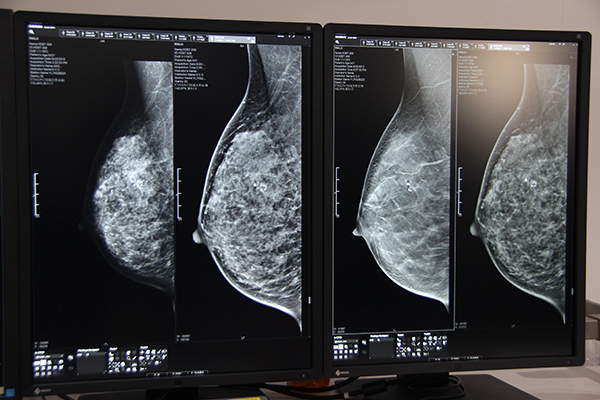

●Women’s Health:多機能化により精密検査を強力にサポートするMAMMOMAT Revelation

Women’s Health エリアでは,ITEM開幕前日の4月12日に発売されたデジタルマンモグラフィシステムMAMMOMAT Revelationの実機と臨床画像を展示した。マンモグラフィシステムはこれまで,精密検査対応の「MAMMOMAT Inspiration」シリーズとスクリーニング対応の「MAMMOMAT Fusion」をラインアップしていたが,MAMMOMAT Revelationはより高度な精密検査のために多機能化が図られている。

Dual Energyとサブトラクション法を使用した造影マンモグラフィ“TiCEM(Titanium Contrast Enhanced Mammography)”を新たに搭載でき,閉所恐怖症などで乳房MRIが受けられない患者に対して造影検査を提供する。造影剤はMRIと異なるため,MRI造影剤にアレルギーがある患者にも造影検査ができる可能性がある。

また,日本人女性に多いデンスブレスト(高濃度乳房)では,マンモグラフィでの検出能が低下することが知られているが,MAMMOMAT Revelationでは通常の撮影と同時に乳腺密度を自動測定する“Insight BD(Insight Breast Density)”を実装することで,客観的な乳腺密度データを表示する。撮影後すぐに,超音波診断装置などによる追加検査が必要かを被検者に説明することができ,より被検者に寄り添った検査を提供できる。

バイオプシーも進化し,ステレオバイオプシーだけでなく,トモシンセシスによるターゲッティングが可能になった。同社のトモシンセシスは±25°と大きな振り角(50°)が特長で,2°ごとに曝射して収集した25枚の2D画像から,トモシンセシス画像を再構成する。この広角撮影により,2D撮影では重なってしまう病変を確実に分離できる。 バイオプシーにおいては,簡単な操作で正確にターゲット設定ができるとともに,“InSpect”機能により患者をポジショニングしたまま採取した標本の撮影が可能で,ワークフロー改善に大きく貢献する。

トモシンセシス撮影では,通常2D,“Insight 2D”(合成2D),“EMPIRE”(逐次近似法を用いたトモシンセシス画像),“Insight 3D”(立体的な情報を提供する回転画像)の4種類の画像処理が行われ,いずれもピクセルサイズ85μmの画像を提供する。

精密検査対応のMAMMOMAT Revelation